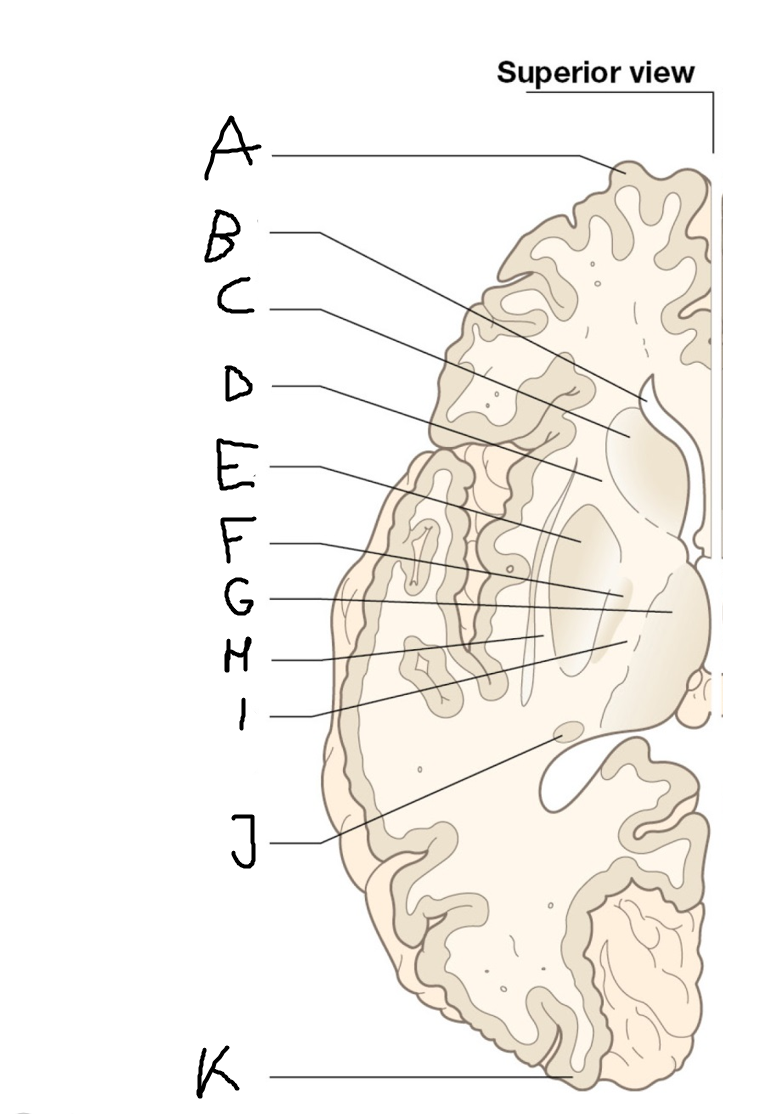

internal capsule (posterior limb)

B

anterior horn of lateral ventricle

C

head of caudate nucleus

D

internal capsule (anterior limb)

E

putamen

F

globus pallidus

G

Thalamus

H

External capsule

I

internal capsule (posterior limb)

J